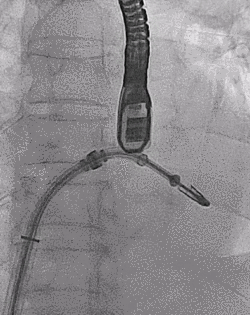

患者全麻以后,在经食道超声心动图和X射线引导下,经股静脉入路,将MitraClip瓣膜夹顺利送至二尖瓣前后叶交界中心处,成功捕捉二尖瓣前叶A2和后叶P2,经超声心动图反复确认瓣叶夹持牢固后,测定有效夹持长度10.4mm,评估反流量降至轻度,释放瓣膜夹,超声心动图评估瓣膜夹位置和功能良好,测定左房压降至26/12mmHg,再次评估反流量仍为轻度,手术顺利完成。

▲ MitraClip释放

王焱、王斌教授团队通过术前和台北荣民总医院(Taipei Veterans General Hospital)宋思贤教授进行了详细的讨论并制定了最优的手术策略,同时术中视频连线获得宋思贤教授的技术支持,主播福利 超声内科苏茂龙教授负责术中超声心动图引导。患者全麻以后,在经食道超声心动图和X射线引导下,经股静脉入路,将MitraClip瓣膜夹顺利送至二尖瓣前后叶交界中心处,成功捕捉二尖瓣前叶A2和后叶P2,经超声心动图反复确认瓣叶夹持牢固后,测定有效夹持长度11mm,评估反流量降至微量,释放瓣膜夹,超声心动图评估瓣膜夹位置和功能良好,测定左房压降至11/6mmHg,再次评估反流量仍为微量,手术顺利完成。